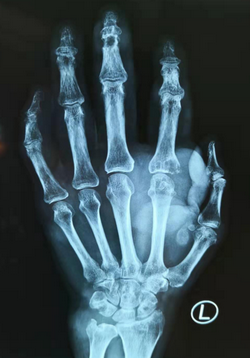

手外科朱辉主任接诊了章大爷,查体发现其双手、双足皮下有数十处结节,尤其是左手食指掌指关节处结节,达10cm×7cm×6cm,触感十分坚硬,皮肤已经很薄,隔着皮肤可以清晰地看到里面石膏样白色质,手部和足部大部分的关节已经无法自由活动。

手外科朱辉主任为患者做了手术。待麻醉生效后先用碘伏消毒,术中再次酒精消毒左手背,接着在左手背肿物中段做斜形切口,切开皮肤,皮下分离,暴露肿物,发现里面全是粉笔灰样物质,对骨质和肌腱皆有不同程度损伤。朱辉主任切下肿物,清除明显沉积物后冲洗切口,为患者止血、缝合并包扎伤口。手术很顺利,患者术后安返病房。